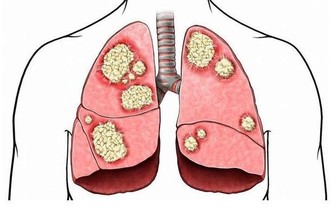

胃:怕冷 胃、十二指腸潰瘍發病有季節性,秋冬和冬春交替都是高發期,寒冷的天氣尤其要注意養胃。胃痛、腹部不適,消化能力降低,這時進食生冷食物就會引起或加重胃部不舒服的症狀。 心:怕咸 食鹽過度會給身體帶來高血壓、心血管疾病等隱患。鹽中含有大量的鈉離子,鈉會引起體內血容量的增加,所以食用過多的鹽,就會導致血壓升高,心臟負擔也會加重。 肺:怕煙 除了吸煙、被動吸煙外,廚房油煙、裝修污染等室內環境污染,也是引發肺癌的危險因素。研究表明,廚房通風不良相比通風良好者,患肺癌風險增加了49%。 腎:怕肉